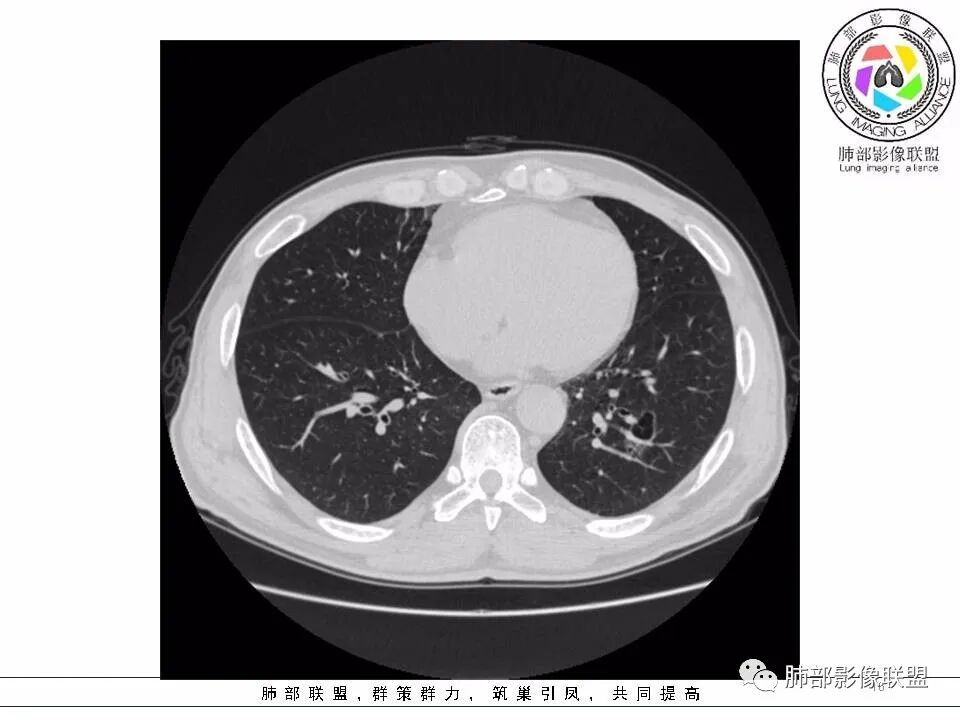

【每日晨读】黄色预警--警惕囊腔型的病变

左肺下叶囊腔,壁厚薄不均,可见磨玻璃成分!考虑恶性可能,腺癌?

左下肺囊性病变,边界不规则,有磨玻璃,内分隔,壁厚薄不均,内有壁结节,考虑囊腔样腺癌。

男性,发热,肿瘤标志物不高,影像:左下肺类圆形囊腔,内有丝丝缕缕,周边有渗出,右肺少许条索,第一印象:囊腔型腺癌

老年男性,左肺下叶囊腔,与临近支气管关系紧密,壁厚薄不均,周围可见实性成分,腔内密度不均匀,可见索条及结节,考虑囊腔型肺癌

男性患者,左肺下叶囊性病变,壁厚薄不均,部分壁较厚,周围可见磨玻璃影,考虑周围型肺癌,腺癌可能。

左下肺囊性病变,边界不规则,周围见磨玻璃影,内分隔,壁厚薄不均,考虑囊腔样腺癌可能性大,鉴别肺大泡合并感染,首次发现建议至少复查一次看看。

中年男性,发热伴咳少量白痰,左下肺可见一囊性空腔,壁厚薄不均,局部周围GGO,边界较清,内见分隔及结节,常规考虑囊腔性腺癌

间断发热半月余。半月前无明显诱因出现发热,体温波动于38℃,畏寒,轻咳,少量白痰,时有活动后胸闷气喘。无胸痛、心慌、乏力、盗汗、消瘦、咯血。于当地诊所予以头孢静脉输注一周,体温正常3天后再次出现体温升高。波动于37.2℃。实验室检查没有太多的问题。左肺下叶囊腔病变,壁比较薄,部分环壁局限性的增厚,边界毛糙,略显模糊,并见与支气管相连,未见明显的壁结节,而囊壁内见丝丝缕缕的索状影。考虑良性病变,毛霉菌感染或隐形性感染,鉴别寄生虫肺部感染。

2.左肺下叶外基底段囊腔样病灶,轮廓柔和,壁厚薄不均,见壁结节。内见分隔或脊状突起。腔内见血管穿行。

这是有“故事”的囊!

3.囊壁外环以磨玻璃影,边界较清楚。

1.囊腔壁厚薄不均,壁结节,内有分隔,其内有血管穿行,指向新生物。

2.临近有边界清楚磨玻璃影,指向腺癌。